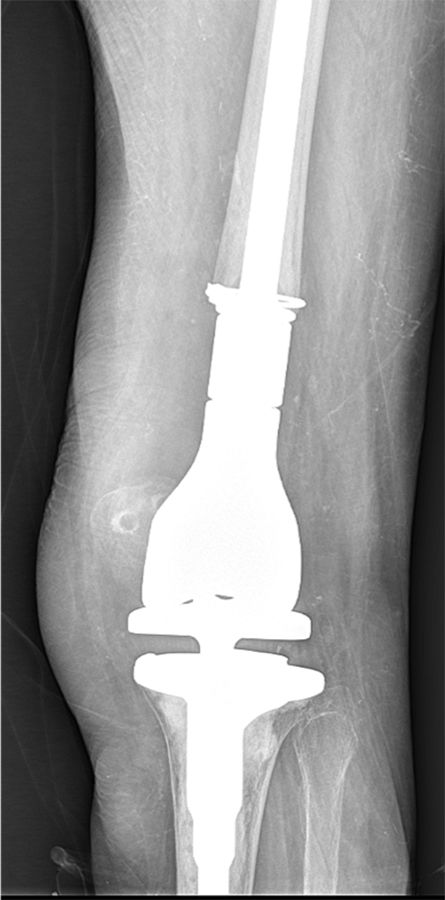

The risk of vascular injury and the difficulty of exposure is less when the femur is subluxated anterior, however, this situation is not without difficulties itself. Usually anterior subluxation of the femur on the tibia results in a significant flexion contracture and significant distal femur resection is needed to allow full extension of the knee and balance flexion and extension space. Based on my personal experience I strongly favor a hinge implant for posttraumatic anterior or posterior dislocations of the femur (Figure 5a, b, c, d).

My rational for this implant choice is that in severe anterior dislocation of the femur, often, the insertion of the collateral ligaments gets compromised when additional distal femur resection is needed to allow full extension. In addition, it is difficult to achieve reliable postoperative range of motion when encountering a knee subluxation in the presence of preoperative stiffness (less than 80 degrees arc of motion). Since the combination of a traumatic dislocation is seldom associated with an addition extraarticular deformity stemmed hinge implants can usually be used without problems.

4. I favor hinge implants for patients with anterior and posterior knee dislocations and an overall arc of motion of less than 80 degrees.